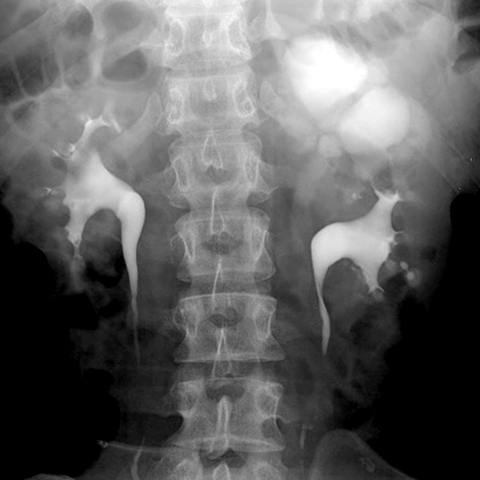

Hydronephrotic kidney, excretory urogram [2 of 2]